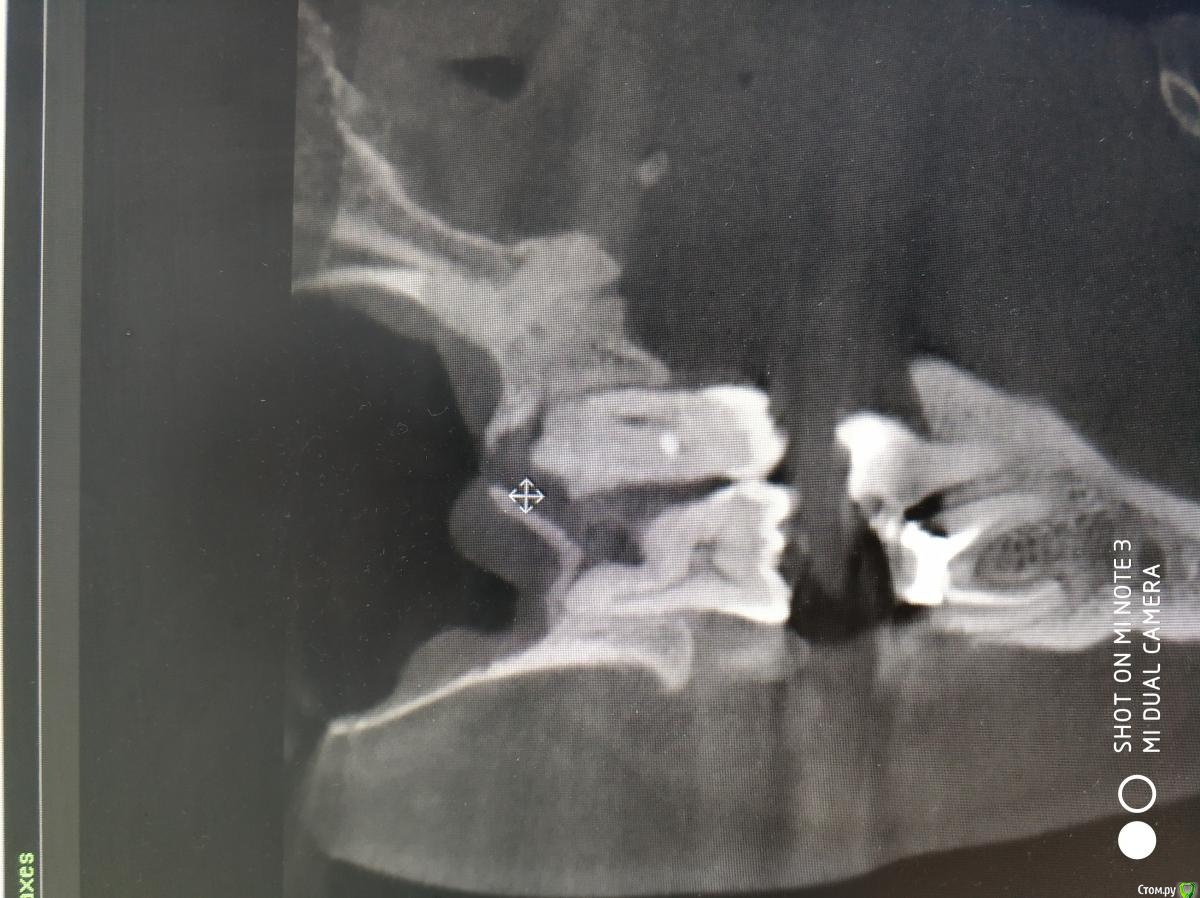

It'sGeorgy Опубликовано 20 февраля, 2021 Поделиться Опубликовано 20 февраля, 2021 А что именно смущает? Что дефект с пазухой сообщается? Так закроете после удаления, ничего страшного. ЛОРу, имхо, там делать нечего пока еще.Недавно был подобный случай: А вообще, судя по тем скринам, которые вы выложили, я бы пациента терапевтам показал для начала. Ссылка на комментарий

Raystom Опубликовано 20 февраля, 2021 Автор Поделиться Опубликовано 20 февраля, 2021 А что именно смущает? Что дефект с пазухой сообщается? Так закроете после удаления, ничего страшного. ЛОРу, имхо, там делать нечего пока еще.Недавно был подобный случай:12.png23.png22.png А вообще, судя по тем скринам, которые вы выложили, я бы пациента терапевтам показал для начала.Именно, что с пазухой. С терапевтами общались, при попытке препарирования зуб "мягкий", как кариозный судя по их словам Ссылка на комментарий

It'sGeorgy Опубликовано 20 февраля, 2021 Поделиться Опубликовано 20 февраля, 2021 Именно, что с пазухой. С терапевтами общались, при попытке препарирования зуб "мягкий", как кариозный судя по их словамну так закроете По поводу способа закрытия скажу вообще непопулярное мнение: я бы просто затромбовал колаполом, дал небольшую подвижность вестибулярному лоскуту и сопоставил края монофилом. Знаю, что это не всегда срабатывает, но меня пока проносило, уже раз 20. Дефект, который сверху выкладывал, закрыл таким же способом. Если недостаточно опыта(как у меня и было), возиться с VIP-CT - не лучшая идея. А вообще, не факт, что там будет ОАС. Часто бывает, что между лункой и пазухой есть тонкая костная пластинка, которой просто на снимке не видно. Ссылка на комментарий